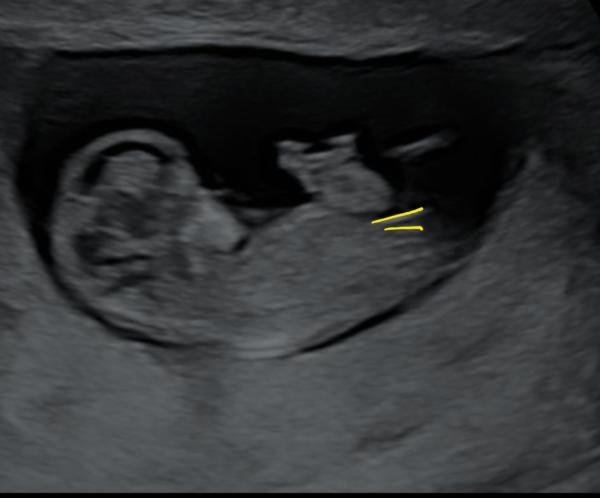

Huhu liebe Letti, ich gucke auch immer mal gerne in die anderen Gruppen rein 🤭 Deine Bilder muss ich wirklich sagen sind sehr schwierig. Würde aber einen Hauch mehr zum Jungen tendieren. Beim Mittleren ist über dem sticht noch ein kleiner kurzer Strich, den haben die Mädels nicht. Ebenso fehlt diese typische Mädchen gabelung vorne. Und bin mir nicht ganz sicher, ob der obere Strich bei (ich glaube bei dem letzten Bild war es) ein ganz kleines mini bisschen mehr nach oben geht. Ich kann es mir aber auch einbilden. Ich muss ehrlich sagen, dass ich die Nub Theorie unfassbar spannend ist und am liebsten den ganzen Tag so Bilder angucken könnte und neugierig bin, was es letztendlich dann ist 🤭

Oh, ich bin ja ganz bei dir. Finde das auch total spannend. Auch wenn das natürlich keine 100% Garantie gibt. Ich muss gestehen, dass ich mich danach ein wenig reingelesen habe und das Ganze trotzdem nicht 100% verstanden habe 🤔😃 Meine Bilder sind aber auch nicht so eindeutig, wie die, die man im Internet (meist) findet. Gerade beim letzten Bild hätte ich eher auf ein Mädchen getippt, weil das für mich so parallel aussah, wo ich eingekreist habe 🥰 Der weiße "Strich/Fleck" oberhalb von dem orangenen Kreis gehört zum Bein. 🤭 Einfach spannend 😍

Ich find es halt interessant, weil die Ärztin bei der Feindiagnostik auch damit anfing und das nochmal erklärt hatte. Schade, dass man den Nub nicht so genau erkennen kann. Oder man kann ihn sehen aber unser ungeschultes Auge bekommt es nicht gebacken 😂 Ich weiß was du meinst. Hab dein Bild frecher weise einfach mal "bemalt" um zu zeigen, was ich meine.

Genau. Das letzte Bild war es. Der untere Strich geht nach unten, der obere nach oben. Es sind nicht beide Parallel verlaufend nach unten.